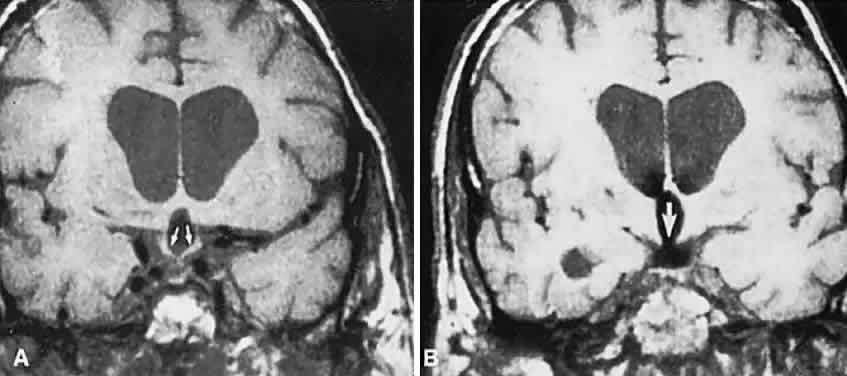

In previous decades, chiasmal interference with optic atrophy, but “normal” plain skull films, was referred to as “Cushing's syndrome of the chiasm,” caused by meningiomas, aneurysms, or other noncalcified suprasellar lesions. The modern neuroimaging techniques of enhanced CT, “bone-window” protocols, and gadolinium-contrasted MRI are now exceedingly sensitive in disclosing meningiomas or other parachiasmal masses (Fig. 4). At present, contrast-enhanced CT or MRI precisely demonstrate extra-axial tumor configuration; CT is superior in disclosing calcification or bone changes, but it is inferior for assessing suprasellar or intrasellar extension, postsurgical changes, and vascular displacement or encasement.76 Whether MRI or even MR angiography obviates standard selective arteriography, especially when surgical intervention is contemplated, is moot.

Fig. 4. Magnetic resonance imaging of a suprasellar meningioma (TR, 600 milliseconds; TE, 20 milliseconds). A. Coronal section of a large meningioma (large arrows), isodense to brain. B. Sagittal section. Note the normal sella and pituitary gland (p). Sagittal (C) and coronal (D) sections of a planum meningioma, extending into the sella. Note the upward deflection of the chiasm (arrow in C) and extension to the cavernous sinus (arrows in D).